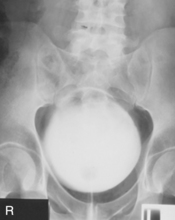

• Supine, midsagittal plane aligned and centered to centerline, support placed under knees, no rotation

• Erect, midsagittal plane aligned and centered to centerline, no rotation

• Center IR to iliac crest—ensure that bladder area, including the symphysis pubis, is included at lower IR margin.